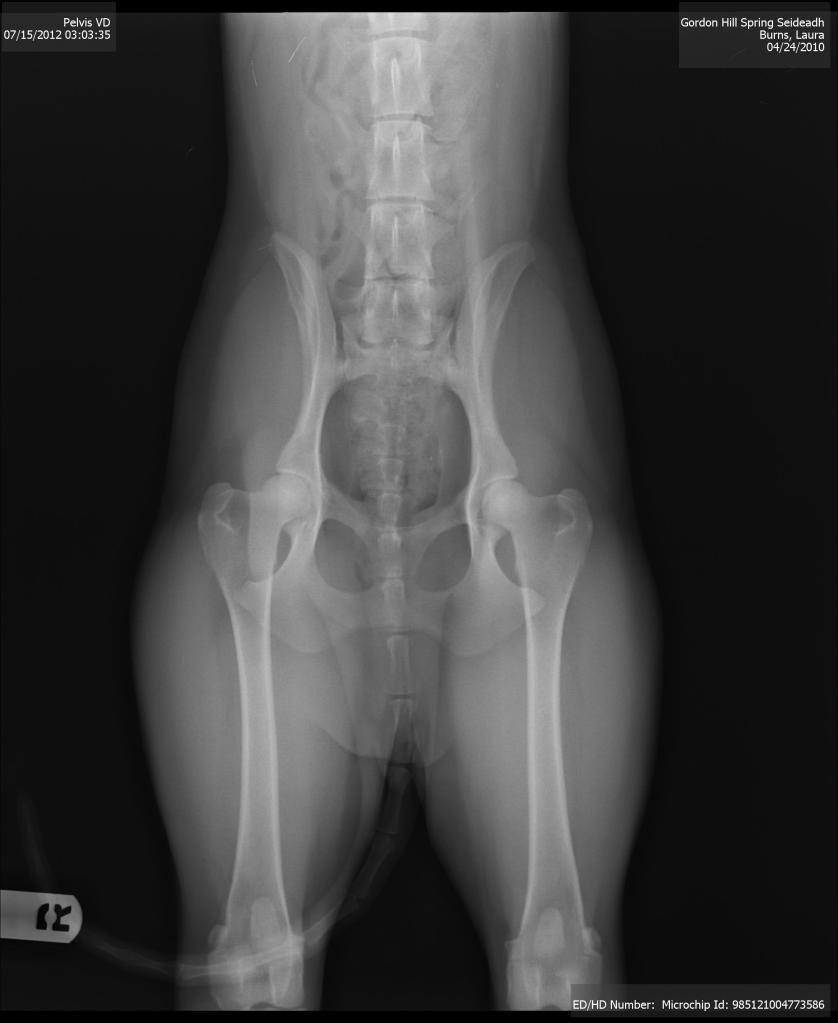

Gael just has her hips and elbows done at Companion Veterinary Clinic in Clearview, WA. This clinic was offering a health clinic with great prices for many standard tests, including hips, elbows, patella, thyroid, heart and eyes. Gael was able to complete her x-rays without sedation, which amazes me when she’s such a wildchild. Here’s her hip x-ray, for those who get as obsessed with these x-rays as I do.

These hips look good! I don’t know everything to look for, but I see deep, tight sockets with no signs of arthritis or other “bony changes.” They look great to me, with my layperson’s eye, and the vet agreed. Here is one of her elbow x-rays, although I have less of an idea of what to look for here: